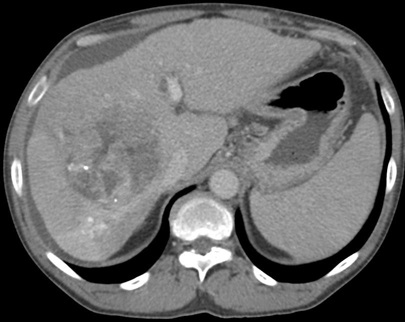

Can see pseudoprogression on CT / MRI as a result of an immunologic infiltrate,More robust T cell infiltration in responders

![]() Greten & Duffy ASCO 2015, ASCO GI 2016, J Heptology 2016